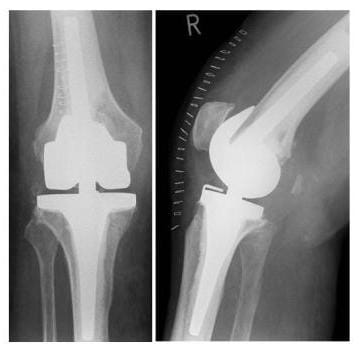

Röntgenbild Bikondylärer Oberflächenersatz

Kompletter Oberflächenersatz mit einer totalen Knieendoprothese: Mit diesem Prothesentyp können die meisten Gonarthrosen behandelt werden. Voraussetzung ist eine ausreichend stabile Bandführung des Kniegelenkes. (Bilder: Orthopädie)